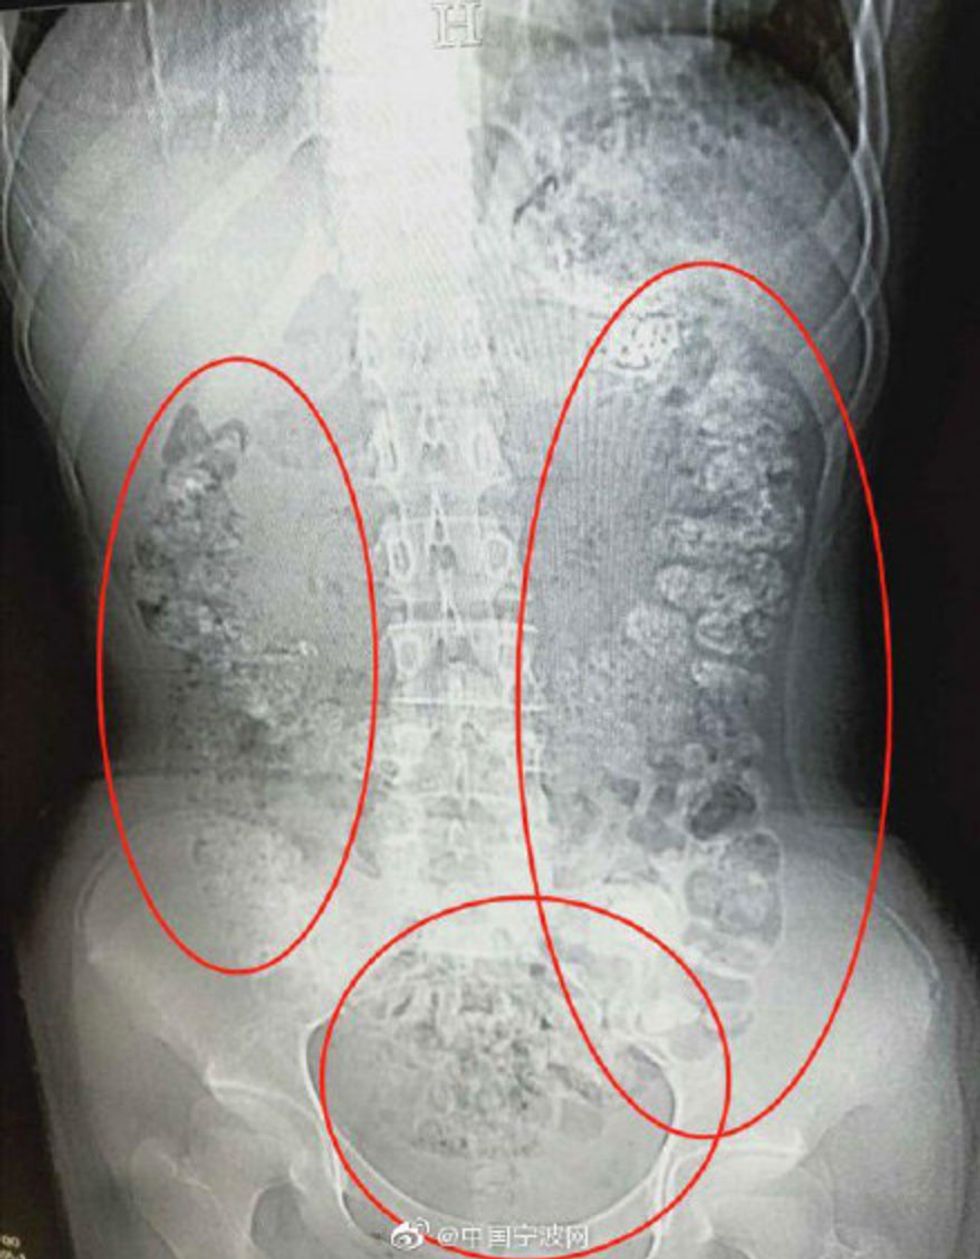

According to reports, the (unnamed) teen, who lives in the Zhejiang province of China, was taken to the hospital when she complained that she'd spent nearly a week in terrible stomach pain and unable to eat. When doctors couldn't find anything wrong with a physical exam, they decided to do some imaging, which (allegedly) led to the following picture:

See those strange, scary-looking shadows? The ones that look like they came directly from PR for a horror movie? Doctors deduced that they were approximately 100 boba pearls that had not been digested. The teen admitted that she'd had one cup of boba in the past few days, but her medical team (and Dr. Gregory House) thought she just might be trying to hide the fact that she'd been scoffing down those pearls like it was her literal job. (Although I've never counted how many pearls you get in a cup of boba. Is it more or less than 100?) (Maybe she digested a whole lot more.)

Alexis Mascitti, a New York-based MD and consultant who I spoke with for this story, told me that while the x-ray above shows "fecal impaction," it's impossible to tell whether the teen's severe constipation came from boba pearls just by looking at the image. Mascitti has, however, seen undigested boba pop up on abdominal x-rays before, so it's not far-fetched that the pearls are the culprit here.